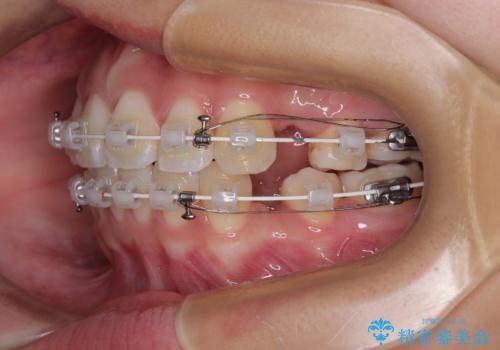

- 矯正装置

- 審美装置

- 2年3ヶ月

- 10-30回